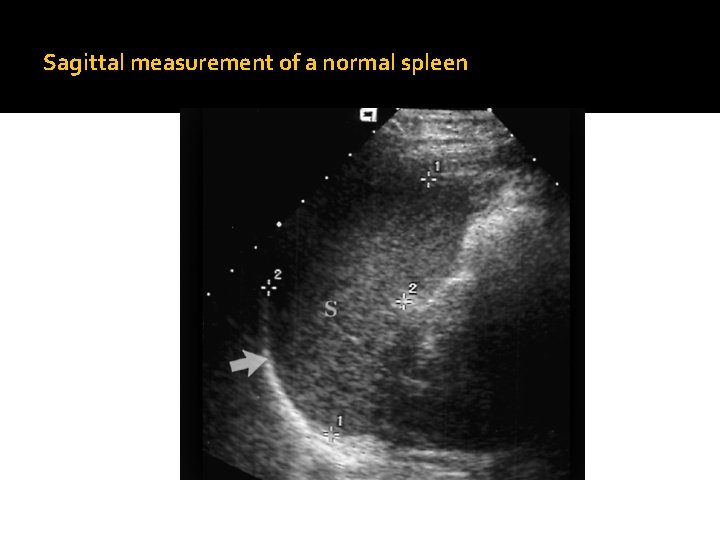

Anatomy and Normal ultrasound appearance, cont… �The spleen is seen as a structure with uniform echo texture and moderate echogenicity and no visible parenchymal vessels. �Splenic vessels may be seen in the splenic hilum. �The spleen is considered to be slightly more echogenic than the liver. �The normal spleen measures less than 12 cm in length in the carnio-caudal (long axis) dimension. �The appearance of the spleen has been known to be called Crescent.

�The parenchymal echogenicity of the spleen varies. The average adult spleen measures: 12 cm – longitudinal 8 cm – transverse 4 cm – thickness

Sagittal Image of a normal Spleen

Sagittal measurement of a normal spleen